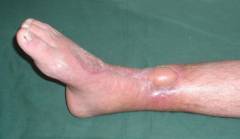

Этот тип остеомиелита возникает, когда слабый микроорганизм не может преобразовать асептический транссудат в гной. Основной признак — выраженная инфильтрация тканей вокруг кости. Несмотря на значительный отек, болезненность остается низкой. На рентгенограммах наблюдается слабая реакция надкостницы с поверхностными фиброзными наложениями.

Клинический местный остеомиелит проявляется интенсивной распирающей болью, охватывающей пораженную кость. При осторожной перкуссии можно выявить область наибольшей болезненности над воспалительным очагом. Нагрузка на кость и движения в соседних суставах ограничены из-за болевых ощущений. Кожа над воспаленной зоной горячая и красная. Яркий отек, особенно при межмышечной флегмоне, вызывает натяжение кожи и блеск. При пальпации над флегмоной может ощущаться флюктуация. Температура тела колеблется от 37,5 до 38,5 градусов. Прорыв гноя через надкостницу в межмышечное пространство облегчает боль. Образование свища приводит к исчезновению болевых ощущений и других признаков воспаления.